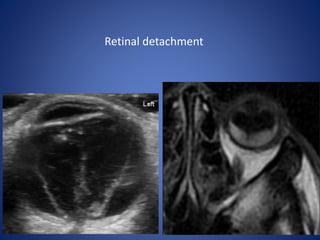

Configuration of collection is cresent shaped or V shaped on axial

sections.

Limbs of V represent detached leaves of retina converging towards

optic disc represent the apex of V.

Collection anteriorly extend upto ora serrata represent anterior

limit due to normal anterior attachment of retina.

Retinal detachment